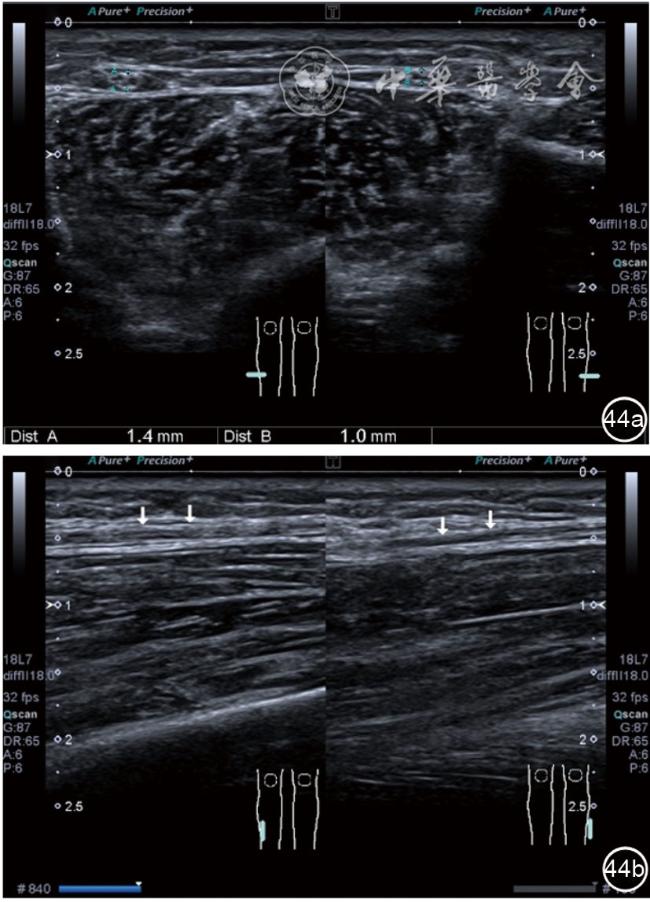

3.超声半定量评估。(1)骨赘超声半定量评估:患者仰卧位,膝关节伸直,探头纵切面置于膝关节内侧与外侧,自前向后移动探头以进行全面扫查。测量骨赘的厚度,并进行半定量分析。0级:无骨赘;1级:小骨赘,厚度<2 mm;2级:中等骨赘,厚度2.1~4.0 mm;3级:大骨赘,厚度>4.0 mm。(2)关节软骨超声半定量评估:患者仰卧位,膝关节完全屈曲。探头置于骨上方,检查股骨内侧髁、外侧髁和股骨滑车处关节软骨三个部位,分别进行横切面和纵切面检查,从近侧向远侧做全面扫查。检查时声束要垂直于股骨表面。关节软骨可按病变严重程度分为四级。0级:关节软骨呈均匀的无回声带,其浅侧和深侧边界清晰。1级:关节软骨浅侧边界不清和(或)内部回声增高。2级:①2A级,关节软骨局部变薄,缺损厚度<50%;②2B级,关节软骨局部变薄,缺损厚度>50%,但<100%。3级:关节软骨局部完全消失,伴或不伴有软骨下骨病变。(3)半月板突出分度:半月板外周缘与胫骨平台边缘之间的距离≥3 mm的突出视为病理变化,诊断为半月板周缘滑脱。按照突出程度分为三度:Ⅰ度,半月板外周缘与胫骨平台边缘之间的距离3~5 mm;Ⅱ度,半月板外周缘与胫骨平台边缘之间的距离>5~8 mm;Ⅲ度,半月板外周缘与胫骨平台边缘之间的距离8 mm以上。

4.腓总神经分支卡压的治疗。常见腓浅神经、腓深神经感觉支卡压。主要表现为足背侧的感觉减退。腓深神经只支配第一、二足趾之间的感觉,腓浅神经支配的感觉区域较多,第一、二足趾之间外的足背感觉均由腓浅神经支配,根据感觉障碍区域确定卡压神经,超声可以明确卡压部位和原因。超声可显示卡压神经增粗,回声减低,局部软组织回声不均匀等(图4445)。治疗以液压松解药物注射为主。以腓深神经为例进行介绍。常见卡压部位在小腿和足背部。根据卡压部位不同,患者采取不同的体位。如果在小腿部采用平卧位,膝关节伸直位即可。穿刺区域常规消毒,探头涂抹耦合剂后套入无菌手套碘伏消毒或使用无菌耦合剂。将探头置于患者皮肤表面,小腿部位采用短轴扫查,确定神经卡压最明显的部位后,用一次性5 ml注射器,应用25G注射针头抽吸0.5%利多卡因4 ml+地塞米松3 mg平面内进针到达神经周围,注意回抽无血液回流后进行注射(图46),完成注射松解,拔出针头,局部压迫3分钟,创可贴覆盖。如果在足背部可以采取平卧位,屈髋、屈膝将足平放于治疗床面。治疗前准备同小腿部,采用长轴显示神经,确定神经卡压最明显的部位后,用一次性5 ml注射器,应用25G注射针头抽吸0.5%利多卡因2 ml+地塞米松1 mg平面内进针到达神经表面进行注射(图47),完成注射松解,拔出针头,局部压迫3分钟,创可贴覆盖。

图44 腓浅神经在小腿中下1/3筋膜穿出部位卡压的短轴和长轴超声图像

图45 腓浅神经在小腿中下1/3筋膜穿出部位局部软组织回声不均匀超声图像